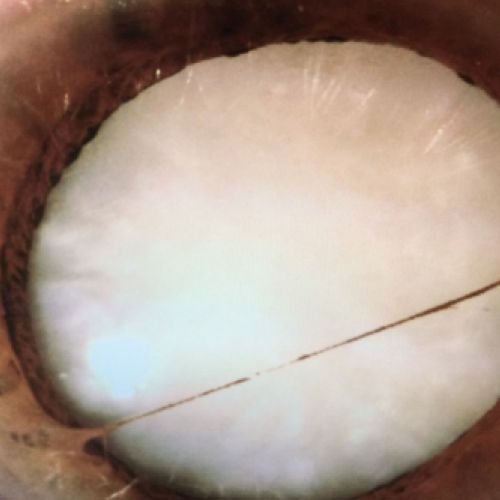

Imágenes de cataratas desde nuestra clínica

Así se ven las cataratas, conoce el caso de algunos de nuestros pacientes

Lente intraocular para corregir una catarata

Cataratas